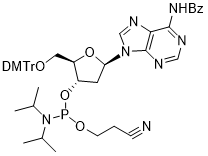

馬鞍山致研生物醫(yī)藥科技有限公司成立于馬鞍山市鄭浦港新區(qū)現(xiàn)代產(chǎn)業(yè)園。公司專(zhuān)注于生物小分子、醫(yī)藥中間體相關(guān)產(chǎn)品的研發(fā)和生產(chǎn),產(chǎn)品主要包括DNA亞磷酰胺單體、RNA亞磷酰胺單體、特殊單體以及按照客戶(hù)要求定制的RNA和DNA,并且公司提供定制合成等方面的研究服...

馬鞍山致研生物醫(yī)藥科技有限公司成立于馬鞍山市鄭浦港新區(qū)現(xiàn)代產(chǎn)業(yè)園。公司專(zhuān)注于生物小分子、醫(yī)藥中間體相關(guān)產(chǎn)品的研發(fā)和生產(chǎn),產(chǎn)品主要包括DNA亞磷酰胺單體、RNA亞磷酰胺單體、特殊單體以及按照客戶(hù)要求定制的RNA和DNA,并且公司提供定制合成等方面的研究服...